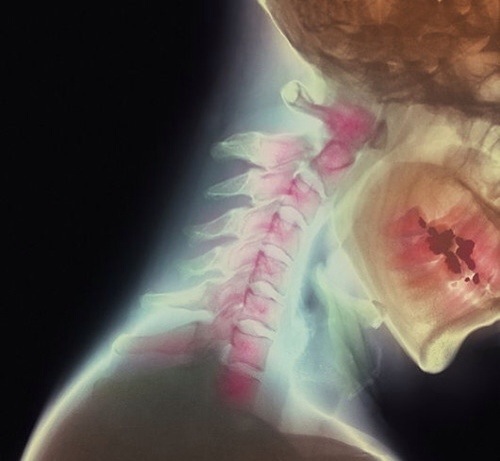

För hör nu här, dessa nysningar är jobbigast och gör ont. Eftersom min muskelbristning i halsen ej har läkt, utan blev värre av att jag försökte arbeta under veckan. Varje nysning snärtar till det hyfsat smärtsamt i halsen, och jag måste självklart nysa sisådär 4-5 gånger i rad innan det går över. Aaaatjoooh! AAAJ! Aaaatjoooh! AAAJ! Och så fortsätter det…